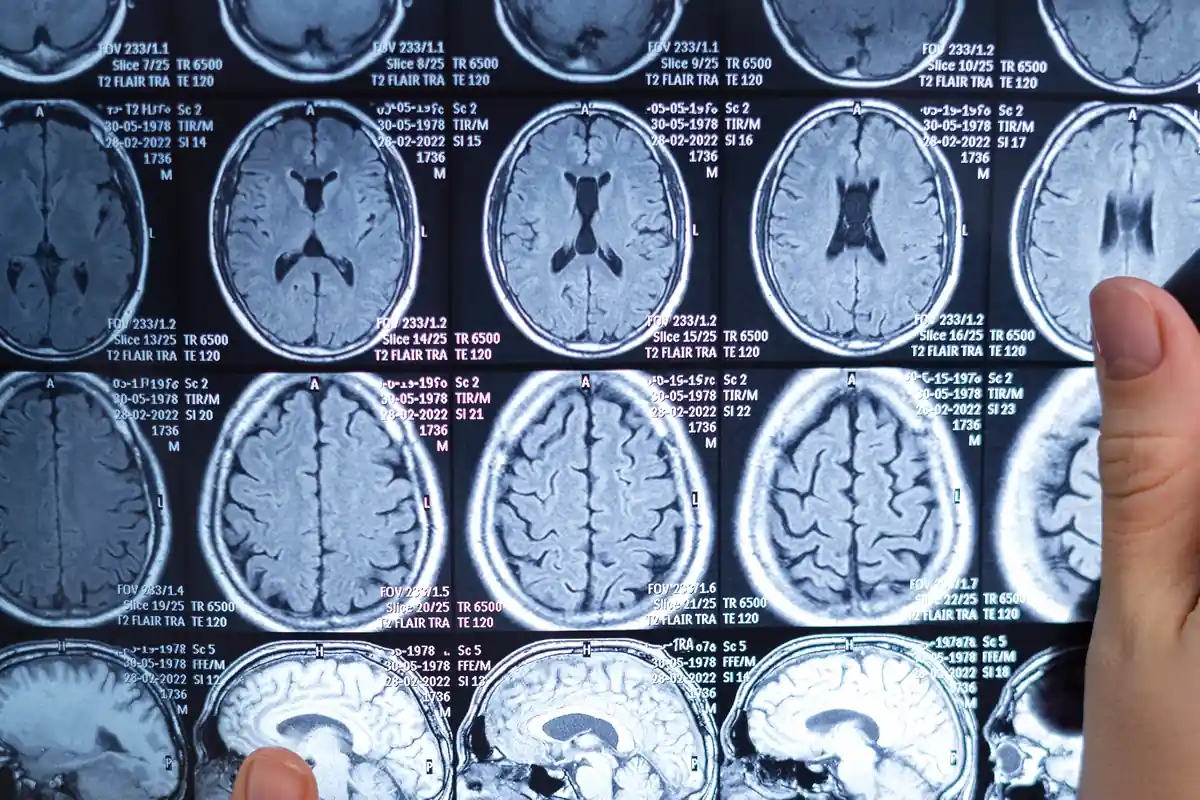

Исследования нейровизуализации указывают на возможную задержку созревания префронтальной коры до трёх лет у людей с СДВГ (Shaw 2007), а также на связь между СДВГ и изменениями объёма и уровня активации в префронтальных областях, связанных с исполнительными функциями (Seidman et al., 2005).

Основываясь на этих открытиях и других клинических результатах, такие авторы, как Браун (2002) и Баркли (2011), предположили, что расстройство СДВГ в основном не происходит из-за дефицита внимания, а является результатом нарушений в синаптических цепях определённых областей мозга, включая префронтальную кору неокортекса, которые играют ключевую роль в регуляции и когнитивном контроле. Следовательно, было сделано заключение, что дефициты в организации и самоуправлении у людей с СДВГ связаны с нарушением исполнительных функций (Barkley, 1997; 2011).